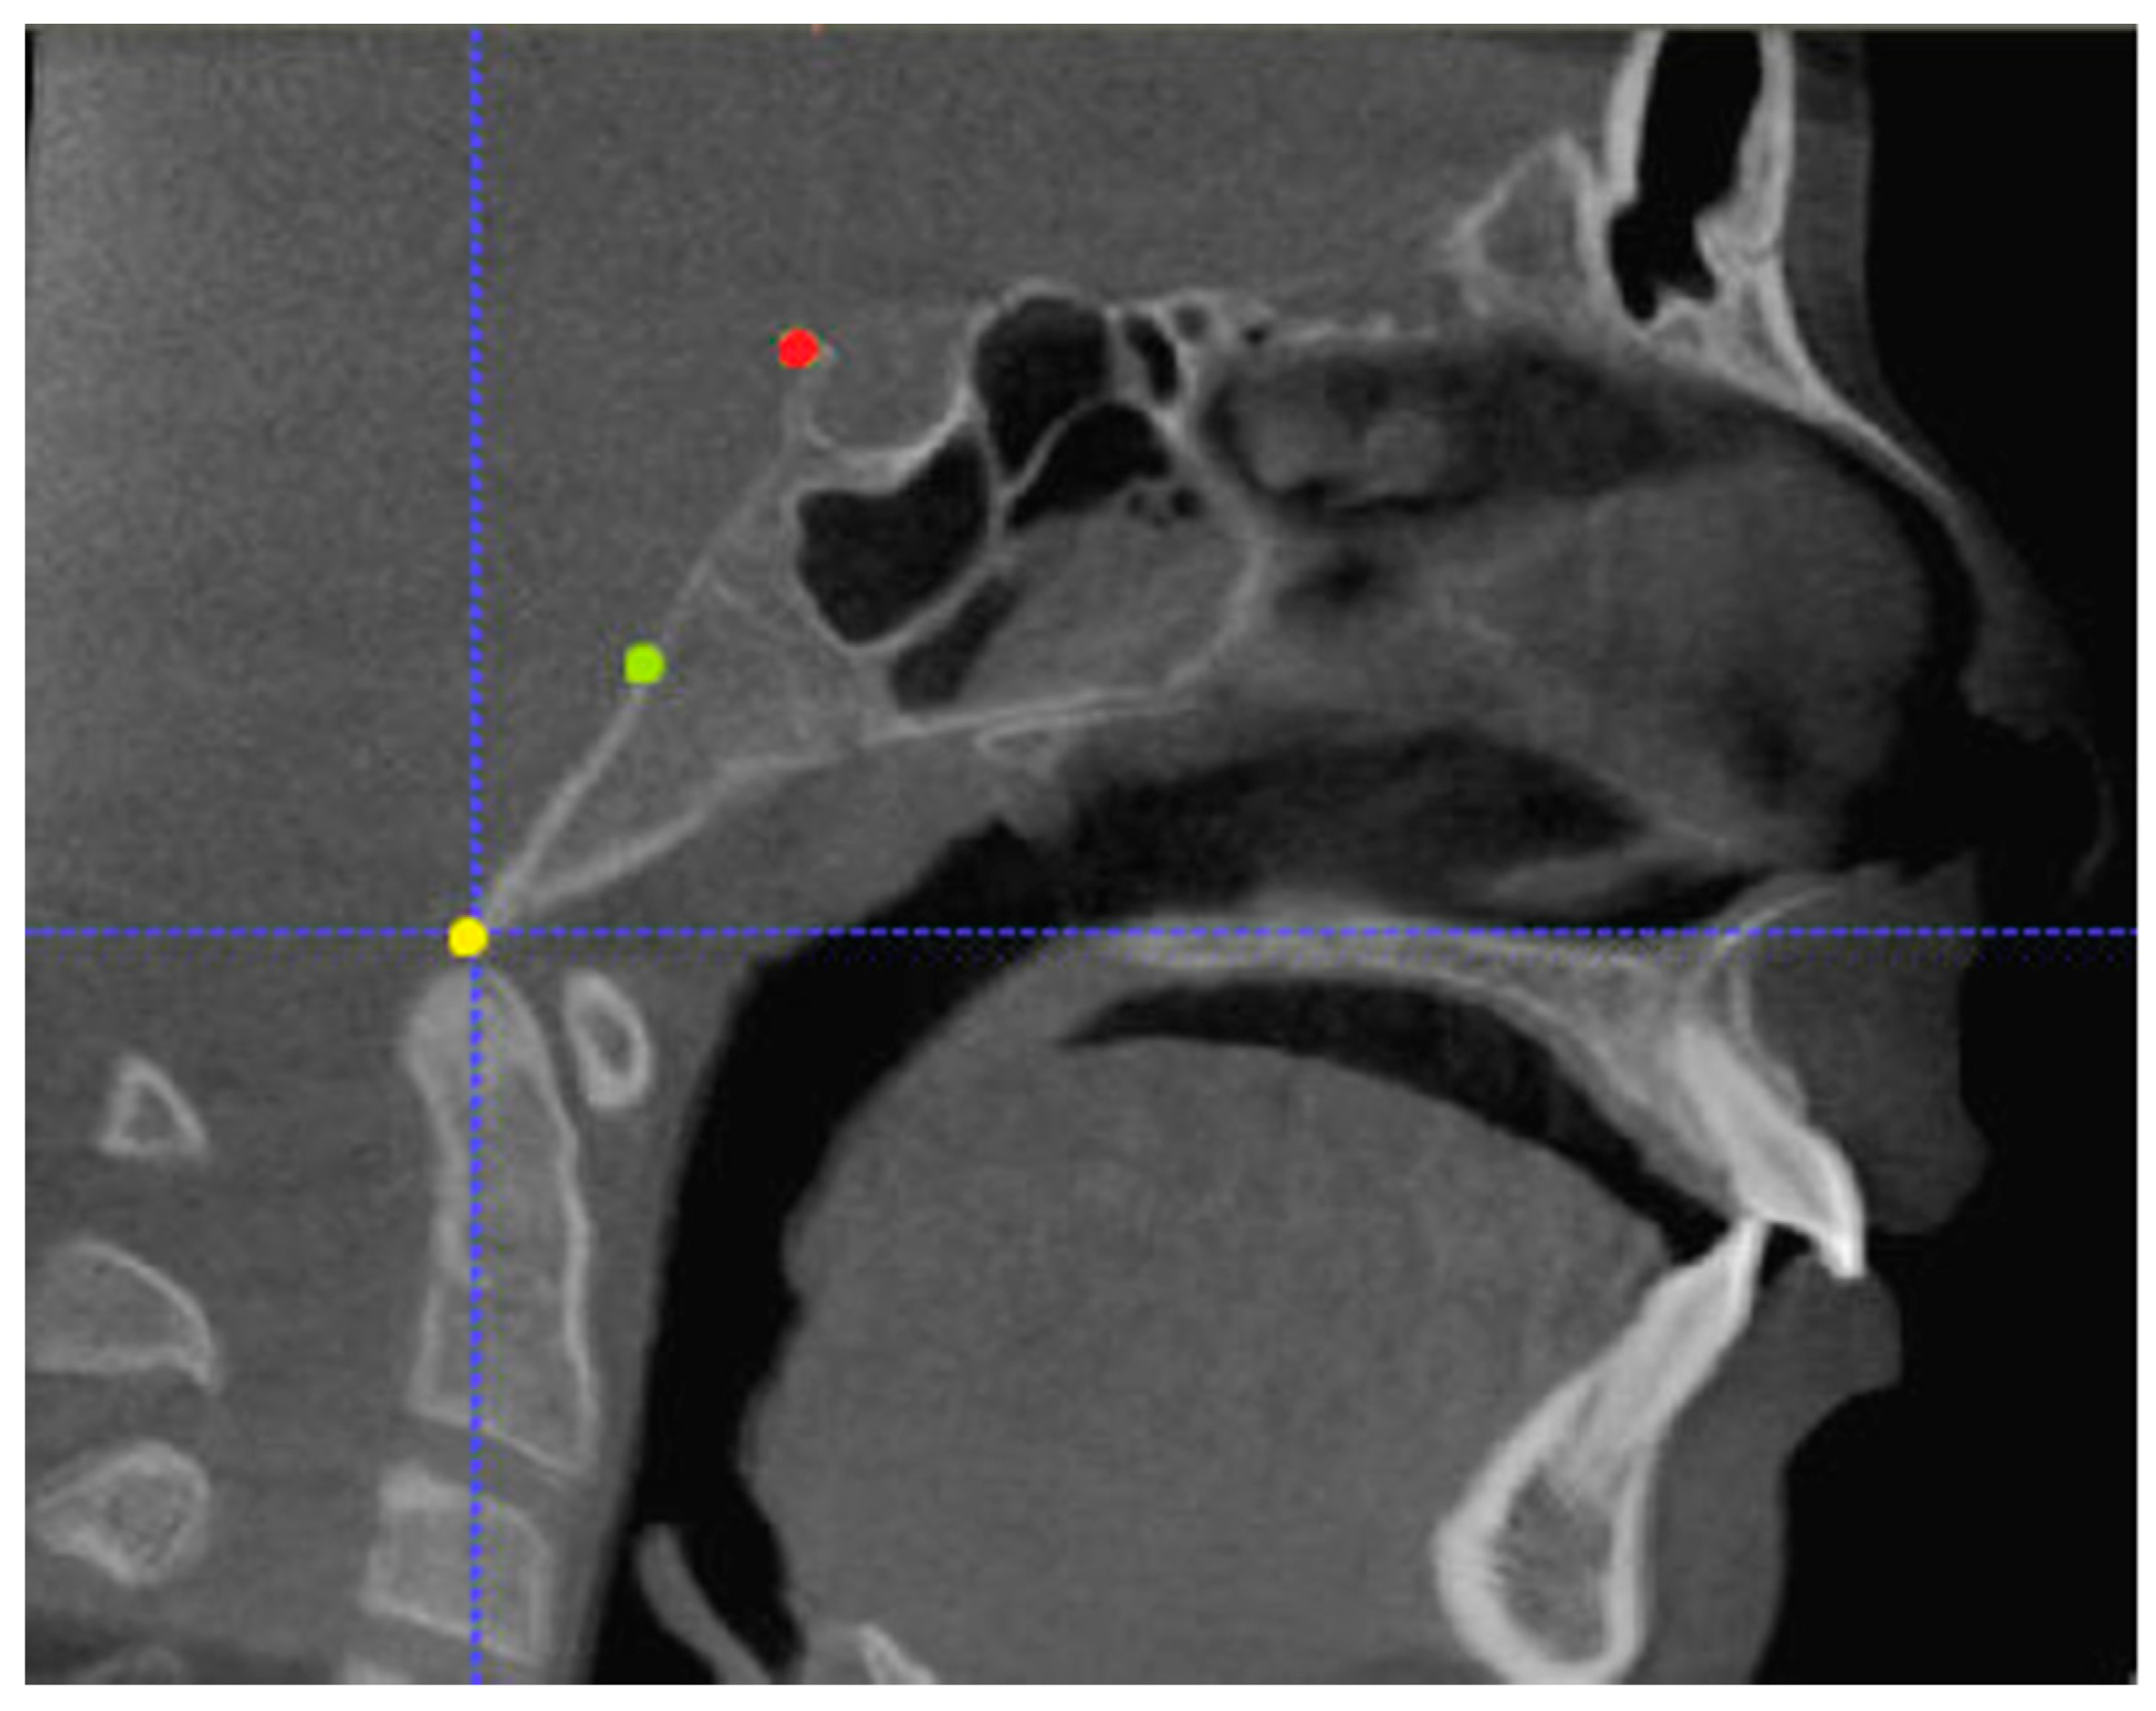

Three points determined the Acta plane: O, F right (FR), and F left (FL) (Table 2). Point O is the midpoint between the most craniodorsal point of the dorsum Sella and the most posterior dorsal point of the Basion in the midsagittal plane (Figure 1). Both points F are a result of the intersection between two lines: the line that connects the most inferior points of the lower orbital margins right and left, and a line perpendicular to this line, that runs through the most external points of the orbital margins, right and left (Figure 2). The new transverse reference plane, the Acta plane (Figure 2), is created by connecting the O-point (Figure 1) with FR and FL (Figure 2).

Figure 1. Point O (green dot) is the midpoint between the dorsum Sella (Se) (red dot) and the Basion point (Ba) (yellow dot).

Point O the midpoint between the most cranio-dorsal point of the dorsum Sella and the most posterior-dorsal point of the Basion in the midsagittal plane.(Figure 1)